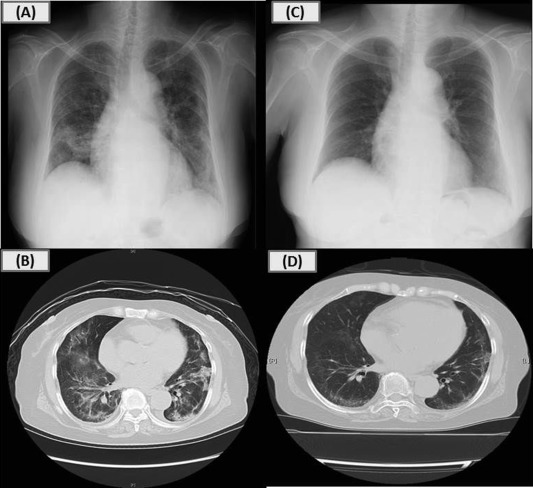

Her physical examination on admission showed bilateral fine crackles with oxygen saturation of 92% on room air, but no fever. Chest radiograph showed bilateral infiltrates (Fig. 1A). Chest CT scan revealed bilateral reticulo-nodular shadows with ground glass opacity (Fig. 1B). Respiratory function test showed moderate restriction with a vital capacity of 1.30 L (%predicted of 60.7%) and a forced expiratory volume in 1 s of 1.23 L (%predicted of 79.9%). Blood test results demonstrated elevated C-reactive protein of 6.69 mg/dL (normal range <0.3 mg/dL), sialylated carbohydrate antigen KL-6 of 585 U/mL (normal range <500 U/mL), and surfactant protein-D (SP-D) of 135 ng/mL (normal range <110 ng/mL). The patients white blood cell counts and proportion of eosinophils were normal. Autoimmune antibodies and specific IgE to garlic were negative. Meropenem and Azithromycin were administered for suspected atypical pneumonia, but were ineffective. Bronchoscopy was conducted in order to make a definite diagnosis. Bronchoalveolar lavage fluid analysis revealed an increased number of total cells and lymphocytes (total cell counts, 34.8 × 104/mlBALF; alveolar macrophages, 17.1%; lymphocytes, 76.1%; neutrophils, 5.0%; eosinophils, 1.8%; CD4/CD8 ratio, 1.3), whereas no malignant cells and microorganisms including fungi and Pneumocystis jirovecii were detected. Transbronchial lung biopsies showed organising exudates, alveolar wall thickening, and lymphocyte infiltrates without granulomas, suggesting organising pneumonia ( Fig. 2).

Chest X-rays and CT scans on admission and after treatment. Chest radiograph on ...

Fig. 1.

Chest X-rays and CT scans on admission and after treatment. Chest radiograph on admission showing bilateral infiltrates predominantly in the middle and lower lung fields (A); Chest CT on admission showing bilateral reticulo-nodular shadows, thickening of bronchovascular bundles, and curvilinear shadow with ground glass opacity predominantly in the middle and lower lung lobes (B); Chest radiograph after 3 weeks of steroid treatment showed significant improvement (C, D).

She was asked to stop taking black garlic and treated with 3 days of methylprednisolone (1 g/day) followed subsequently by oral prednisolone (40 mg/day) because of her aggravating respiratory condition. After the initiation of treatment, chest radiographs showed significant improvement (Fig. 1C,D). In terms of blood abnormalities, SP-D recovered to normal within 9 days while KL-6 showed a transient increase at day 18 and then returned to normal at day 36. She was instructed not to take any kinds of garlic and discharged. At the outpatient clinic, oral prednisolone was tapered and stopped over 9 months. No recurrence has been observed up to the present.